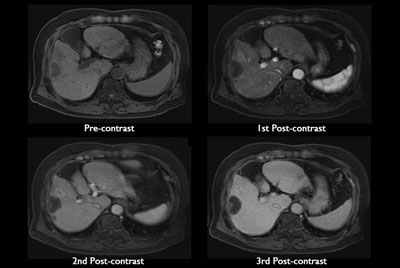

SmartSpeed Liver